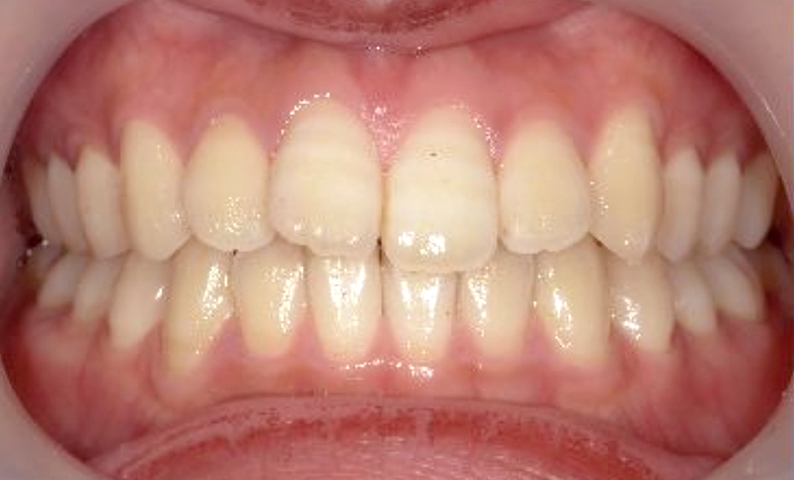

症例_001 前歯「捻転歯」症例

治療期間:6ヶ月金額:48万円+税20代女性少しのねじれ捻転歯下の八重歯

| Before | After |

|---|---|

|